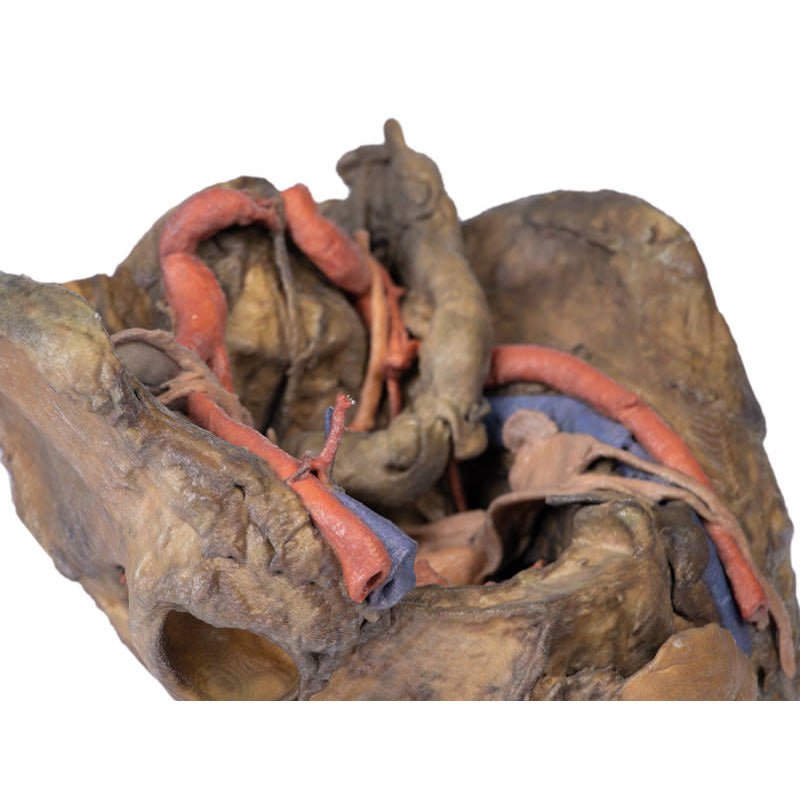

This 3D model presents a deep dissection and isolation of the pelvis from surrounding regions, particularly

demonstrating visceral and neurovascular structures relative to deep ligaments and osseous features.

Lateral to these organs, branches of the internal iliac artery can be identified – as well as a retained median

sacral artery in the midline between the two common iliac arteries. On the left side only the uterine artery can

be seen laterally. On the right side, the obturator, superior vesical, and uterine arteries can be observed. In

addition, the origins of the inferior epigastric artery and vein can be seen arising from the external iliac

vessels just prior to exiting the inferior abdominal cavity.